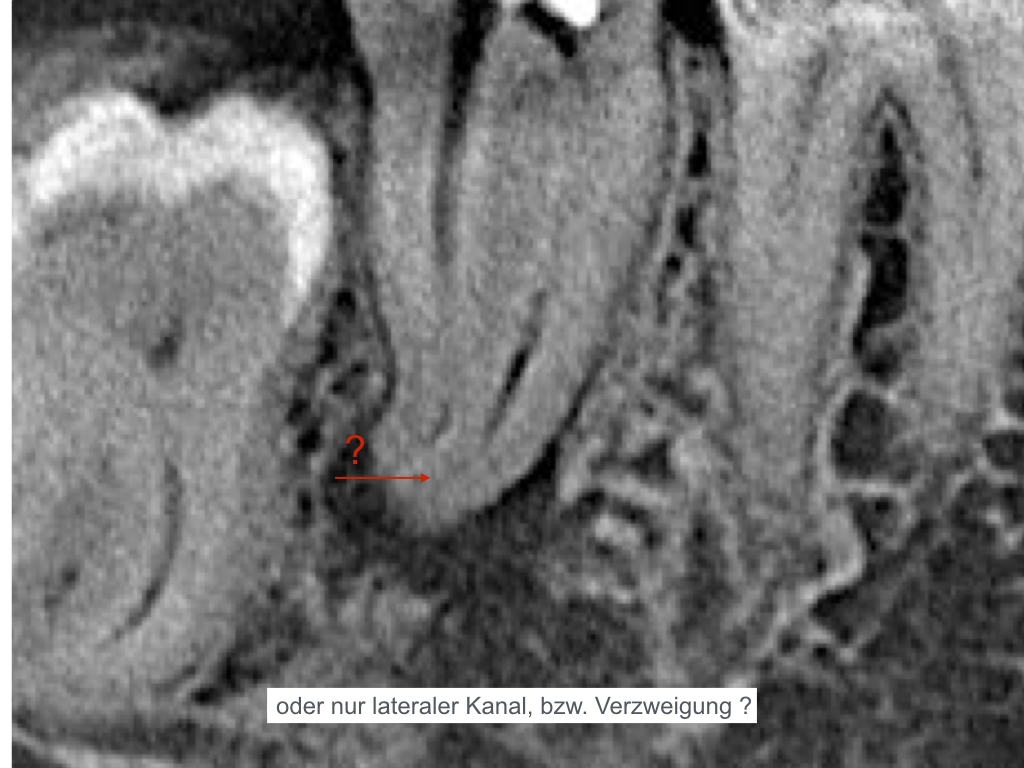

ws-15092016-005

Handinstrumentierung